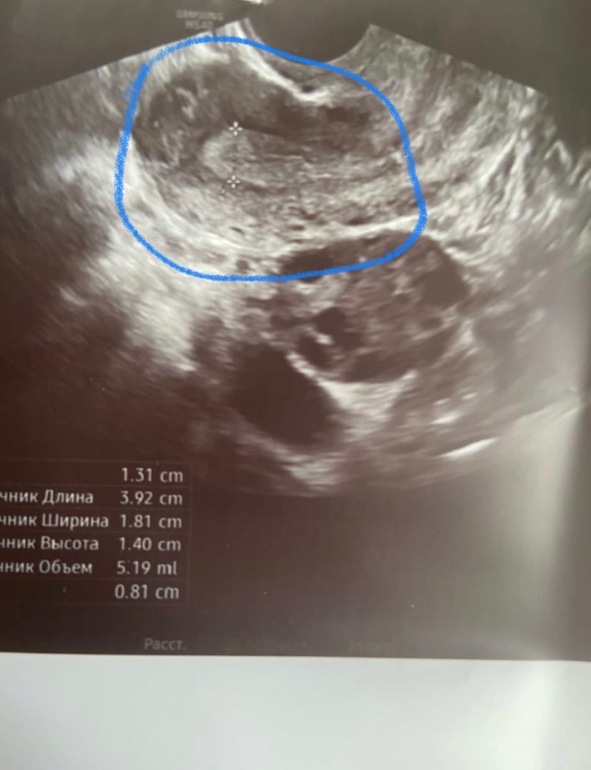

Фото узи. Неровные края.. может ЖТ?

Но как вам края фолликула? Или просто снимок размазался. Я дотошная. Завтра уже успокоюсь, но что думаете?

Судя по снимку это ЖТ. Фолик даже если он регресирует по другому выглядит. Да еще видно ведь что вокруг ЖТ есть ободок, у обычного фолика стенки тонкие. А жидкости может и не быть уже, тк она рассасывается в течении 1-4дней после овуляции.

Ну врач у Вас конечно. Если сдулся фолик это значит регресировал. А совулировал это вообще другое. И ЖТ начинает образовываться сразу же, только постепенно меняя свои размеры и структуру. И у Вас прям видно что это ЖТ. У вас уже и жидкости за маткой нет.

То что фоллик сдулся, сказала узистка, просто мой врач работает в первой пловине дня, я не смогла к ней попасть. А сегодня я ей рассказала, она сказала что меньше рамер (14 мм), потому что Жт образоваться не успело, что позже оно будет больше. Я видимо не правильно написала здесь. Только вот верхнее фото - это типа должн быть ЖТ. А нижнее фото-это какой он был прям перед уколом..

У меня закрались сомнения. Вы говорите про ЖТ, о верхнем фото или о нижнем?

На нижнем фоллик 21 мм, а сверху как раз что то непонятное. Вы о верхней фотке???